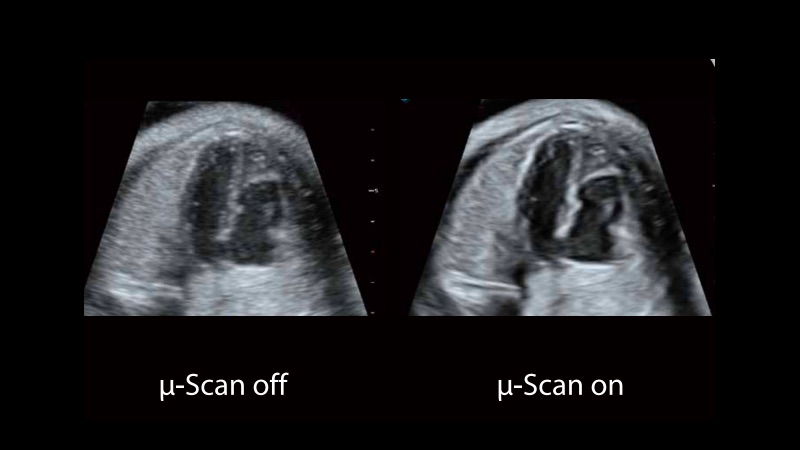

新一代微米成像技術(shù)大大提高了器官和病變的可見(jiàn)性。高清對(duì)比度分辨率將抑制斑點(diǎn)噪聲,同時(shí)保持真實(shí)的組織結(jié)構(gòu)。